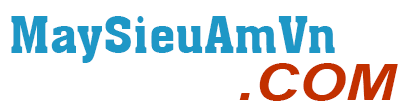

Máy siêu âm Doppler màu 4D SonoScape S11 được thiết kế với màn hình LCD có độ phân giải cao 15 inch với cánh tay khớp nối nhanh và thiết kế xe đẩy nhanh, 4 cổng cắm đầu dò hoạt động sẵn, ứng dụng trong Duplex, Doppler màu, DPI, PW Doppler, hình ảnh hài hòa mô, sp-scan đốm lốm đốm, hình ảnh toàn diện

• Duplex, Doppler màu, DPI, PW Doppler, hình ảnh hài hòa mô, giảm sp-scan đốm

Chế độ quét 2D rõ nét, lưu lượng máu nhạy.

Công nghệ hình ảnh 3D tự do và âm lượng 4D.

– Hệ thống Doppler màu đáng tin cậy,

– Công nghệ chính: Hình ảnh hợp chất không gian, Hình ảnh toàn cảnh, Giải phẫu M –Mode, hình ảnh 3D tự do, hình ảnh 4D (một số trong số đó là tùy chọn.)